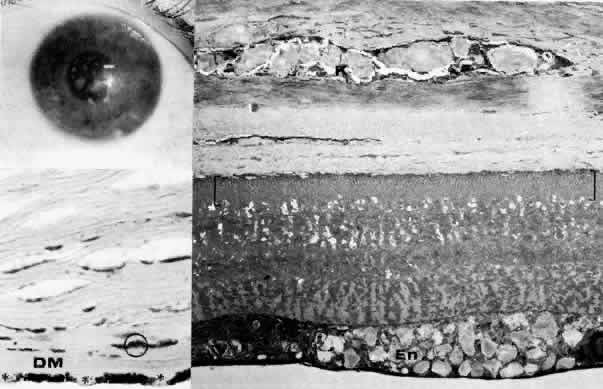

Initially described by Maumenee173 in 1960, this congenital disorder of the endothelium is characterized clinically by diffuse, bilaterally symmetric corneal edema (Figs. 5 AND 15; Color Plate 1J). The autosomal recessive variety is present at birth and is relatively stationary. Symptoms of discomfort are not prominent despite profound epithelial and stromal edema. Nystagmus is common.174 A dominantly inherited form is less severe, developing in the first or second year of life, and, in contrast to the recessive variety, progressive photo(text continues on p. 27) phobia and tearing are the initial symptoms. Nystagmus is generally absent.174 As in all instances of congenital corneal clouding, it is important to rule out congenital glaucoma.

Fig. 15. Congenital hereditary endothelial dystrophy. Top left. Clinical photograph of eye of a 14-year-old male with severe form of the dystrophy shows diffuse ground-glass stromal opacification. Top middle. In a mildly affected 20-year-old female, the cornea has moderate diffuse haze and visual acuity is 20/200. Top right. On slit lamp biomicroscopy, diffuse edematous thickening of the corneal stroma is evident in same patient as top middle photograph. Middle right. Light microscopy of a case with uniformly thickened (approximately 35μm) Descemet's membrane (DM) covered posteriorly by extremely attenuated endothelial cells (arrowheads). S, posterior stroma; AC, anterior chamber (hematoxylin-eosin, × 600). Bottom left. Transmission electron micrograph of same case as middle right micrograph reveals anterior portion of Descemet's membrane (DM) to have normal thickness and banded structure. The markedly thickened (approximately 20 μm) posterior layer exhibits both 55 nm and 110 nm banding (circled) interspersed with homogeneous material. En, endothelial cell; AC, anterior chamber; S, posterior stroma (× 9200). Bottom right. At higher magnification, the abnormal posterior zone is seen to consist of multiple laminations of basement membrane-like material (*) and fine filaments. En, endothelial (× 42,000).

The degree of edematous corneal clouding varies from a mild haze to a milky, ground-glass opacification. Epithelial microbullae may be obvious, and stromal thickness may be increased threefold or more. Uniform thickening of Descemet's membrane is sometimes evident on clinical examination, but no guttata are apparent. Interstitial inflammation and secondary vascularization are absent. There are no definitely associated ocular or systemic abnormalities.

Histologic study175–181 reveals nonspecific anterior and stromal changes consistent with long-standing secondary edema: basal epithelial cell swelling, basement membrane thickening and disruptions, and irregularities of Bowman's layer with pannus formation. However, it may be significant that, in some cases, ultrastructural examination discloses greatly enlarged stromal collagen fibrils sometimes measuring as much as 60 nm in diameter. Descemet's membrane is uniform in a given specimen; it may display diffuse thinning of 3μm to massive thickening of 40 μm (normal thickness is 3 to 5 μm in neonates and 8 to 10 μm in adults). The anterior banded layer of Descemets membrane is always present and of relatively usual thickness; however, the posterior layer consists of multilaminar basement membrane-like material with fine filaments and of collagen fibrils with a 55- and 110-nm banded configuration. With the exception of the lack of guttata, these findings are similar to those in Fuchs' dystrophy and thus represent another example of posterior collagen layer formation by either primarily or secondarily abnormal endothelium.18,41,43,181, It is postulated that in cases with thin Descemet's membrane, complete endothelial loss occurred in utero such that only the fetal anterior portion of Descemet's membrane was secreted.180 In contrast, cases exhibiting thickened Descemet's membranes may be the product of dystrophic but persistent endothelium having secreted a hypertrophic posterior collagen layer.

The frequent finding of enlarged stromal collagen fibrils suggests some primary developmental abnormality of both keratocytes and endothelium, thus perhaps qualifying this disorder as another example of mesenchymal dysgenesis.22